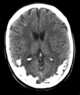

Familial occipital calcification and epilepsy